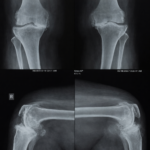

Knee replacement surgery involves removing the arthritic bone from the thigh bone (femur) and shin bone (tibia). The removed bone is replaced with metal and special plastic. During the surgery, the arthritic bone underneath the knee cap is also removed and replaced with a plastic button. The prosthesis utilizes the patient’s native ligaments and muscles for movement and stability.

Total knee replacement surgery is an inpatient procedure that is performed using general/Spinal anesthesia. Your doctor will make an incision, exposing the bone beneath. Damaged cartilage and a small amount of the bone will be removed and replaced by metal implants that are either cemented or pressed into the bone. Finally, your doctor may resurface your patella and insert a smooth spacer into your joint to facilitate fluid movement. The entire procedure usually takes no more than 1 or 2 hours.